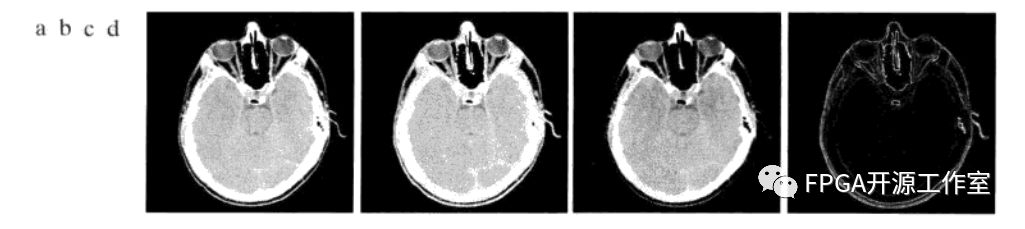

圖2 CT掃描頭部圖像

如圖2所示,a為頭部CT掃描圖像,b為膨脹后的結(jié)果,c為腐蝕后的結(jié)果,d為形態(tài)學(xué)梯度。計(jì)算圖b與圖c的差得到圖d,圖d顯示出了區(qū)域間的邊界被清楚地描繪出來(lái)。這與二維微分圖像的預(yù)期結(jié)果相同。